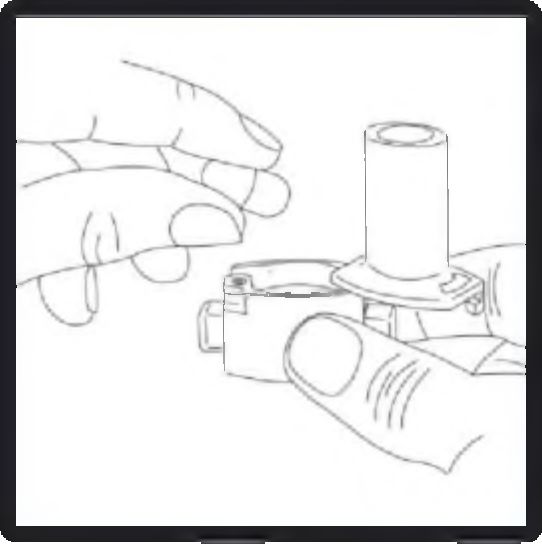

3. Kapsülü, ambalajından kullanmadan hemen önce çıkarın. Cihazın tabanındaki kapsül şeklindeki hazneye bir kapsülü yerleştirin.

4. Ağız parçasını kapalı konuma getirmek için çevirin.

5. Cihazı dik tutun (ağız parçası yukarıda olacak şekilde) ve kenardaki çıkıntılara eş zamanlı olarak SADECE BİR KEZ basın. Bu şekilde kapsül delindikten sonra kenar çıkıntılarını bırakın. Lütfen dikkat: Bu işlemi yaparken jelatin kapsül parçalanabilir ve soluma sırasında küçük jelatin parçalarının ağız ve boğaza kaçma olasılığı vardır. Jelatin parçaları zararsızdır ve yutulduktan sonra hazmedilir. Kapsülün kullanımdan hemen önce ambalajından çıkarılması ve kapsülü patlatmak için kenar çıkıntılarına sadece bir kez basılması jelatin kapsülün parçalanma riskini en aza indirir (bkz. 3. basamak).